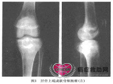

主要是X线表现,相当典型,尤其当肿瘤位于骨骺部位时。软骨母细胞瘤的溶骨区开始位于骨骺,...